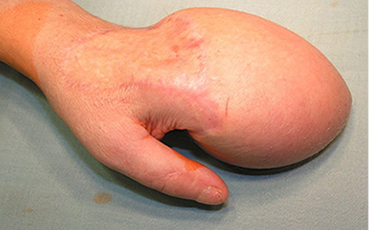

1 pav.

2 pav.

Kairės plaštakos minkštųjų audinių Degloving amputacija. Nugarinis ir delninis paviršiai (1 ir 2 pav.)